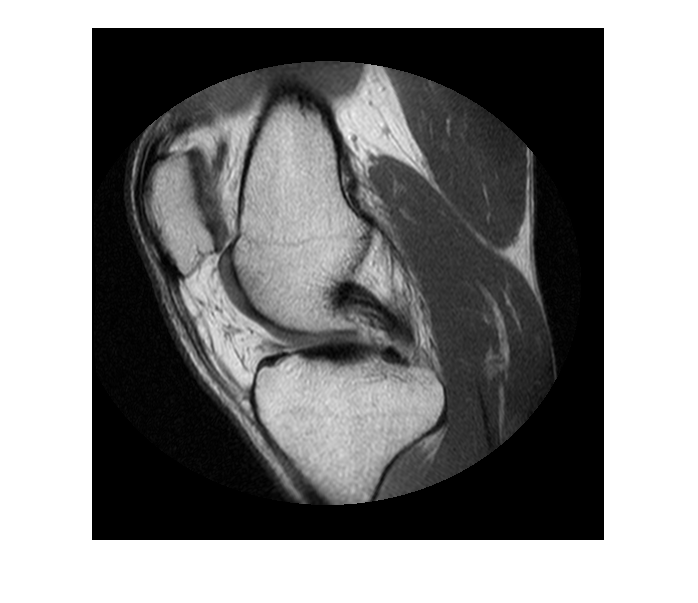

Считайте данные MRI в рабочую область.

im = dicomread('knee1.dcm');

Сегментируйте изображение MRI и выберите две самых больших области маски.

segmentedLabels = imsegkmeans(im,3); boneMask = segmentedLabels==2; boneMask = bwareafilt(boneMask, 1);

Отобразите изображение.

figure hImage = imshow(im,[]);